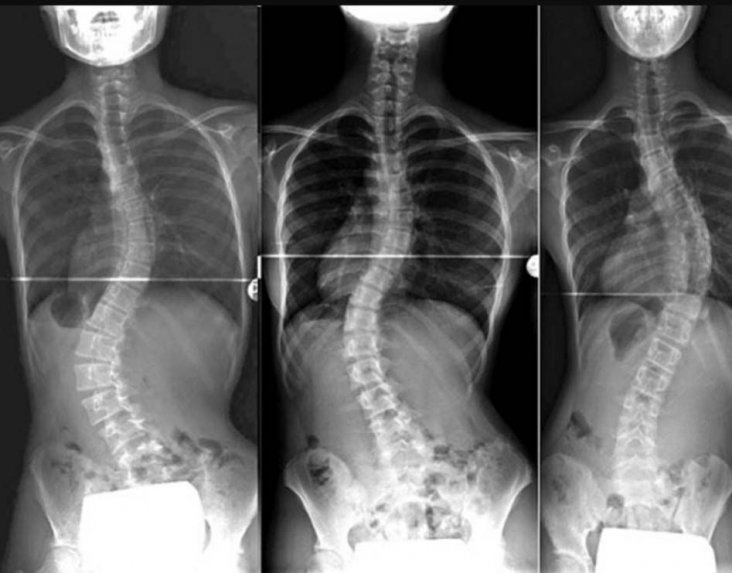

¿Qué es exactamente la escoliosis?

La escoliosis es una desviación lateral de la columna, acompañada normalmente por una rotación de las vértebras.

Cada caso es distinto: algunas personas tienen curvas muy pronunciadas, otras apenas visibles, algunas tienen dolor; otras, no.

La escoliosis es una condición tridimensional.